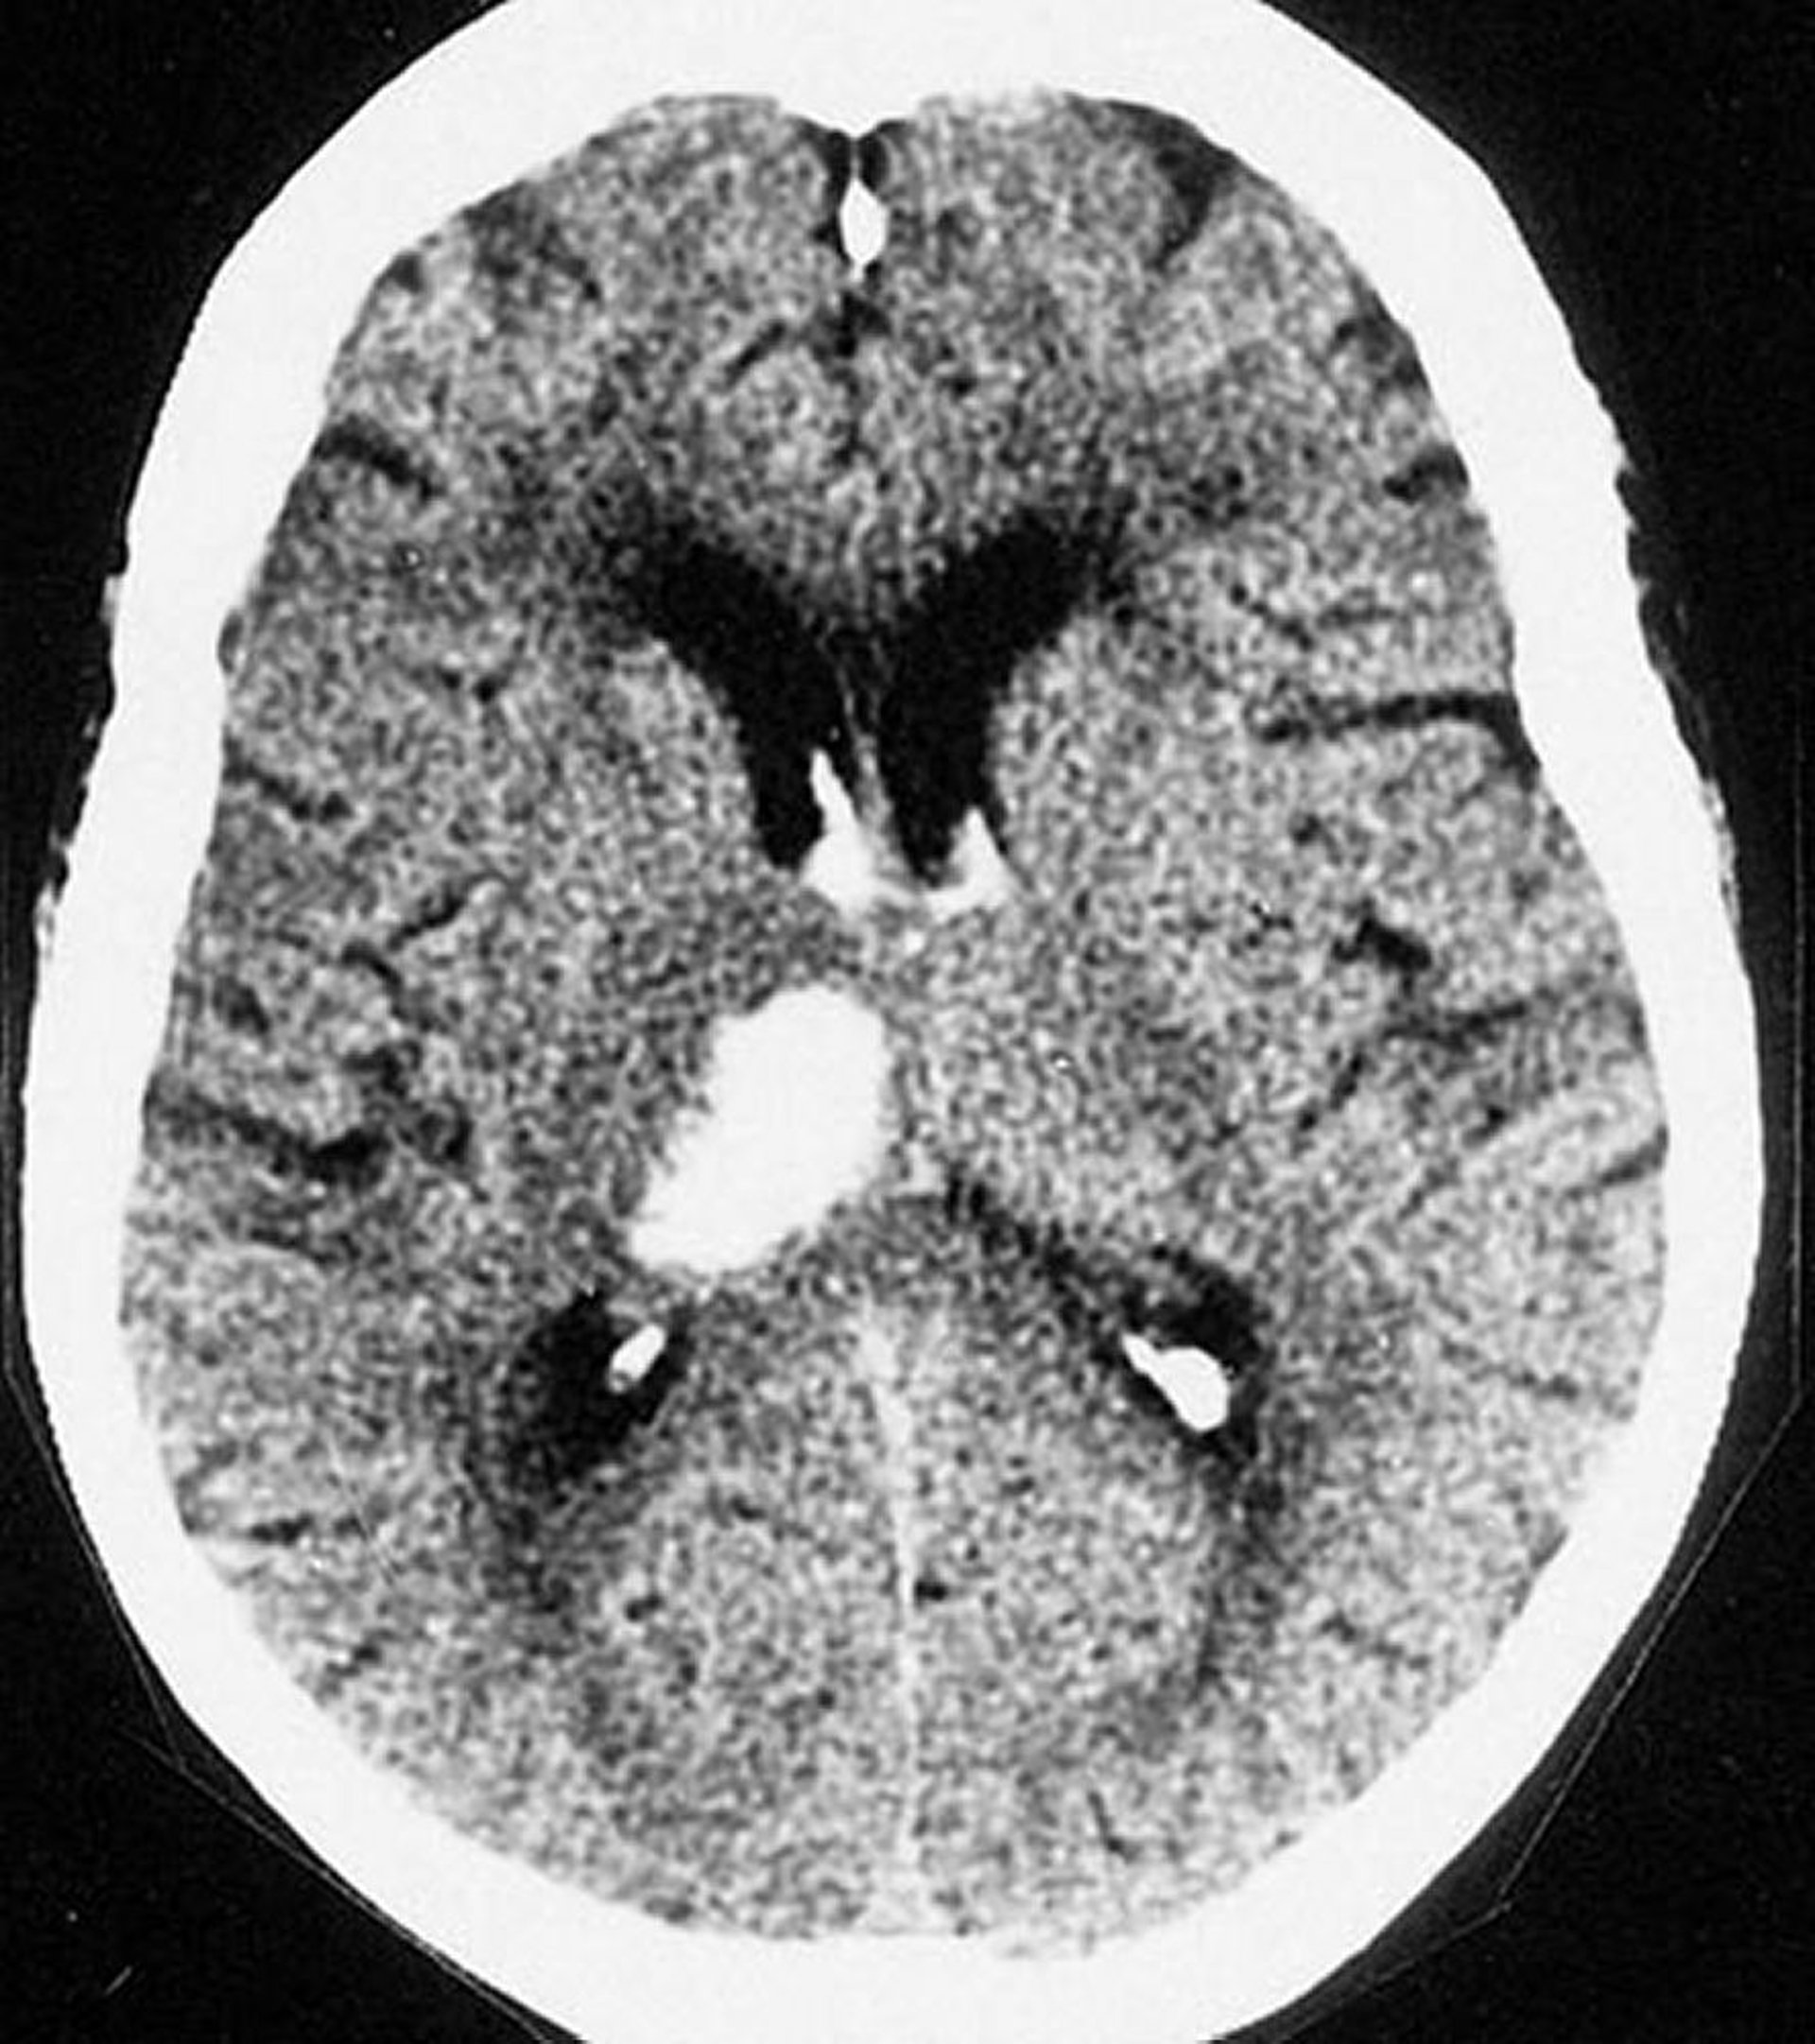

Emorragia intracerebrale talamica

Questa scansione TC mostra un'emorragia nel talamo. Le emorragie intracerebrali si verificano di solito nel talamo e nei gangli della base.

By permission of the publisher. From Furie K, et al. In Atlas of Clinical Neurology. Edited by RN Rosenberg. Philadelphia, Current Medicine, 2002.